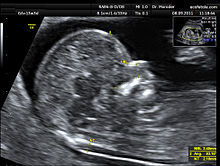

Entre las pruebas de cribado, se incluyen las siguientes: Prueba de la traslucencia nucal. Esta prueba, que se realiza entre las semanas 11 y 14 de embarazo, utiliza la ecografía para medir el grosor del pliegue nucal, ubicado detrás del cuello del feto. (En los bebés con síndrome de Down y otras anomalías cromosómicas se tiende a acumular fluido en esa parte, lo que hace que el pliegue sea más grueso.) Esta medida, junto con la edad de la madre y la edad gestacional del bebé, se puede utilizar para calcular las probabilidades de que el bebé tenga el síndrome de Down. El triple cribado o el cuádruple cribado (también conocidos por sus nombres en inglés: "triple screening" o "quadruple screening"). Estas pruebas miden las cantidades de diversas sustancias en la sangre materna. Como indica su nombre, el triple cribado analiza tres marcadores, mientras que el cuádruple cribado incluye un marcador adicional y es más exacto. Generalmente se practican entre las semanas 15 y 18 de embarazo. Cribado integrado (también denominado cribado secuencial o screening integrado). Esta prueba utiliza los resultados del cribado del primer trimestre (con o sin los resultados de la prueba de la traslucencia nucal) junto con los resultados del cuádruple cribado del segundo trimestre para recoger la estimación más precisa posible en términos de cribado. Ecografía de alta precisión. Se realiza una ecografía detallada del feto cuando tiene de 18 a 20 semanas de edad gestacional, junto con un análisis de la sangre materna. En esta prueba se determina si el feto presenta los rasgos físicos asociados al síndrome de Down.